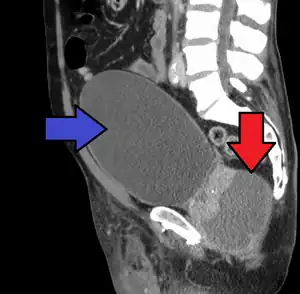

Abscess of the prostate (red arrow) resulting in urinary retention (blue arrow) -

People who are severely ill may need hospitalization, while others can be treated at home with bed rest, analgesics, stool softeners, and hydration. Men with acute prostatitis complicated by urinary retention are best managed with a suprapubic catheter or intermittent catheterization. Lack of response to antibiotics should raise the suspicion of an prostate abscess and prompt an imaging study such as a transrectal ultrasound (TRUS).[10]